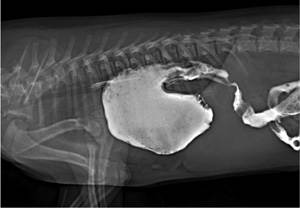

Наиболее показательным диагностическим тестом является рентгенограмма легких. Характерно затенение контура сердца, смещение, деформация легочных долей, разрыв диафрагмальной линии, перемещение печени, петель кишечника в грудную клетку.

Для лучшей визуализации и более точной оценки степени повреждения проводится контрастная рентгенография. Собаке выпаивается специальный раствор, который окрашивает стенки кишечника в белый цвет. Это позволяет очень четко рассмотреть, какая именно часть кишечника оказалась в грудной клетке. Также метод используется при минимальных повреждениях, спорных случаях.